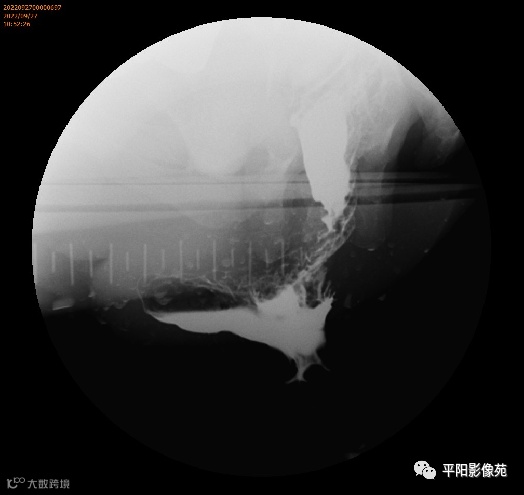

病史:肛周间断性肿物脱出15年,加重伴便血3月

症状:肛周间断性肿物脱出15年,加重伴便血3月,排便

长,大便干结

肛周截石位视诊:3、7、11点痔核环状脱出,血管曲张明显,6点见肛管梭形溃疡。

指诊:肛周6点触痛,未及皮下结节;肛门括约肌收缩良好,齿线附近及痔区粘膜饱满,肛管及直肠未扪及其他肿物,指套无血染,直肠前突明显大于3cm。肛门镜:因疼痛未完成。

排粪造影

排便造影钡(x射线)排便造影或排便直肠造影是诊断排便障碍的公认临床

钡排粪造影实时评估直肠壁形态、盆底运动和排空。